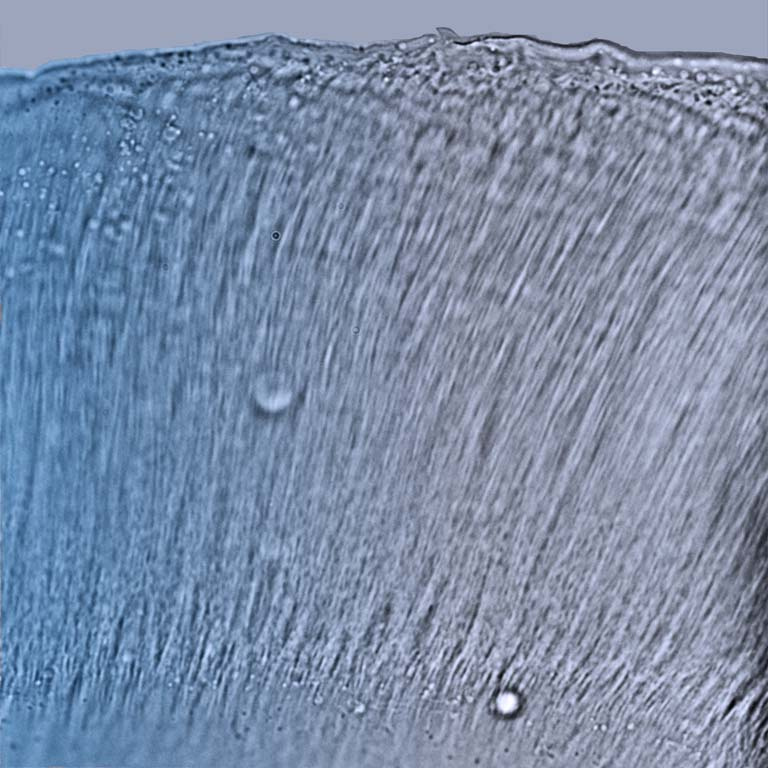

This image is a single frame from a stroboscopic video depicting wave motions on the tectorial membrane––a hydrogel that overlies hair cells in the inner ear. As sound waves enter the ear they are transmitted from the middle ear bones to the fluid filled inner ear, also known as the cochlea. Within the cochlea there are tiny receptors called hair cells that transform this mechanical energy into electrical signals that the brain can interpret. The last mechanical step in this cascade involves the propagation of waves on the tectorial membrane to stimulate these hair cells. Our goal was to understand how the underlying molecular properties of the tectorial membrane contribute to its wave properties and how these in turn contribute to our ability to parse out sounds of different frequencies.